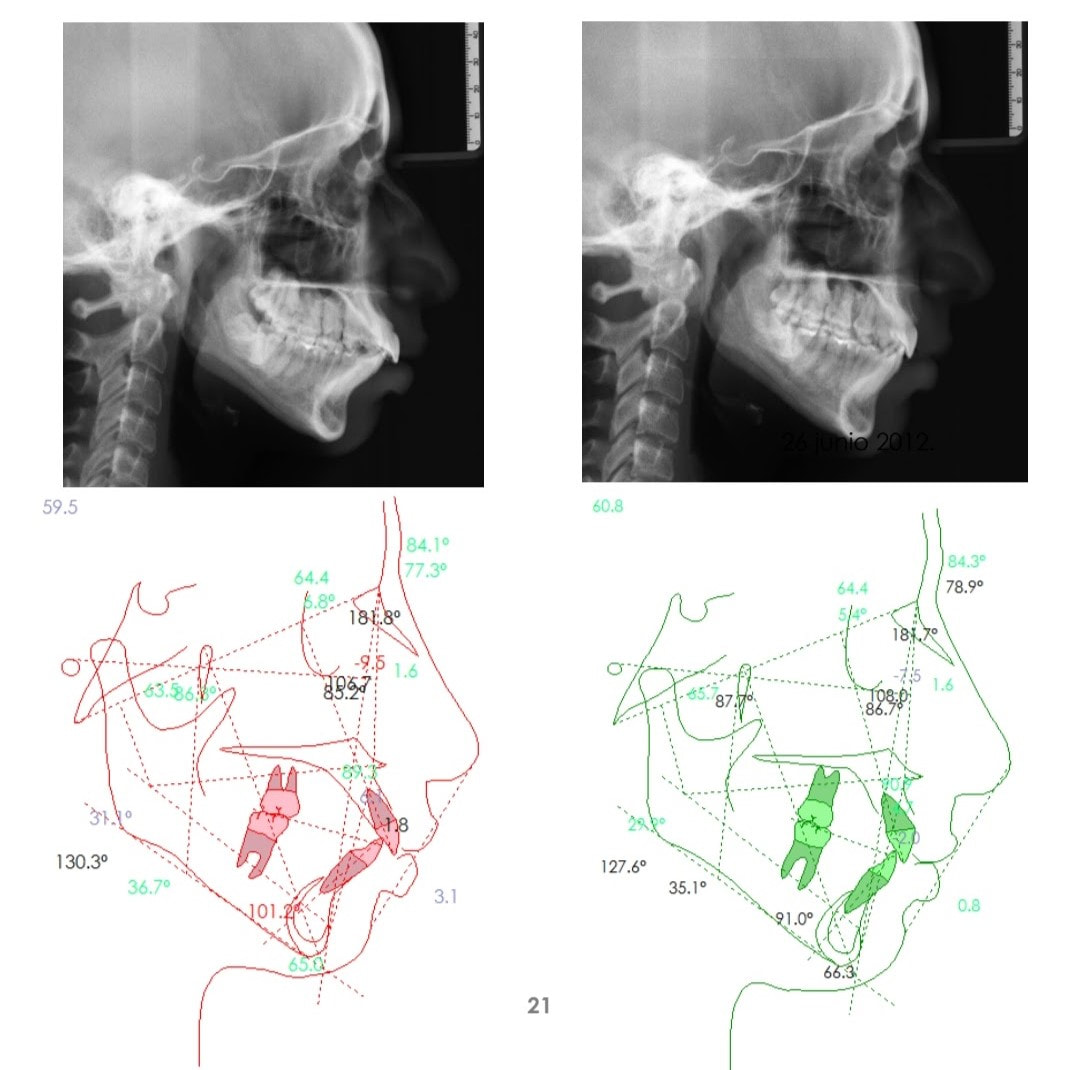

Casos